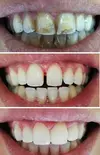

تسوس الأسنان

تطبيقات البورسلين

فينير اللامينيت